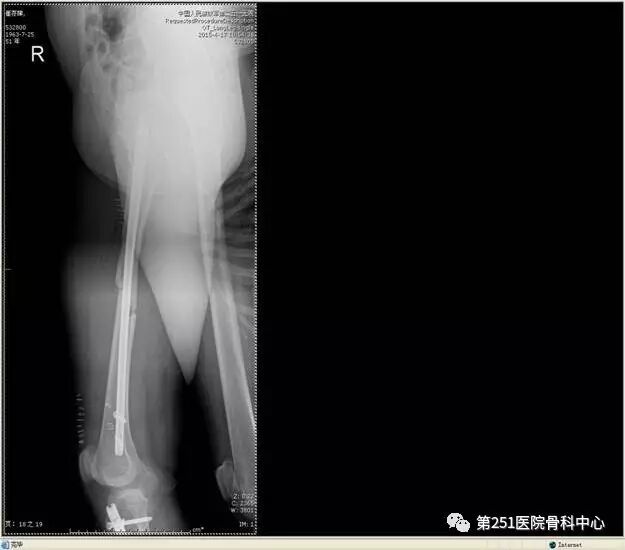

病例4:女性,车祸伤,同侧股骨、股骨颈合并胫腓骨骨折。

![]()